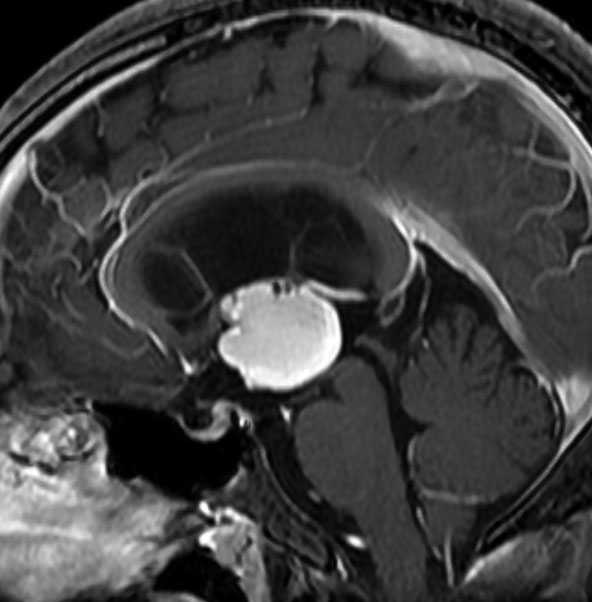

5歳の時に発見され23歳まで18年間経過観察をされてきた患者さんです。腫瘍はゆっくり,しかし確実に増大して,手術前には頭痛がひどく薬も効かず歩けなくなったという症状でした。術後に頭痛が無くなったので,のう胞による症状だったのでしょう。

下垂体柄の周囲にのう胞性腫瘍があります。T1強調画像では等信号,T2強調画像ではまだらな信号になっています。23年という長い経過から液状内容物が固形化したものと推定されます。T2で低信号となる部分があるのですが,黄色肉芽腫とは異なる像です。

下垂体柄は長く伸びています。のう胞による長期の圧迫のため斜台上部がerosionになって凹んでいます。トルコ鞍内の中間葉の位置に典型的な小さなラトケのう胞(黄色矢印)がみられますが,これは長年変化していませんでした。

左前頭側頭開頭 pterional approachで,のう胞壁を含めて完全摘出 complete removalしました。のう胞は下垂体柄の左側に付着してそこから発生したものでした。内容物は固体で寒天状のコロイドでした,一部軟らかくて一部は線維化していました。のう胞壁は半透明で薄い部分も線維性の膜状の部分もありました。病理検査では上皮細胞が証明されて内胚葉のう胞 endodermal cystの診断です。

ラトケのう胞はhiatusから内容液吸引だけして,皮膜はもちろんそのままにしています。